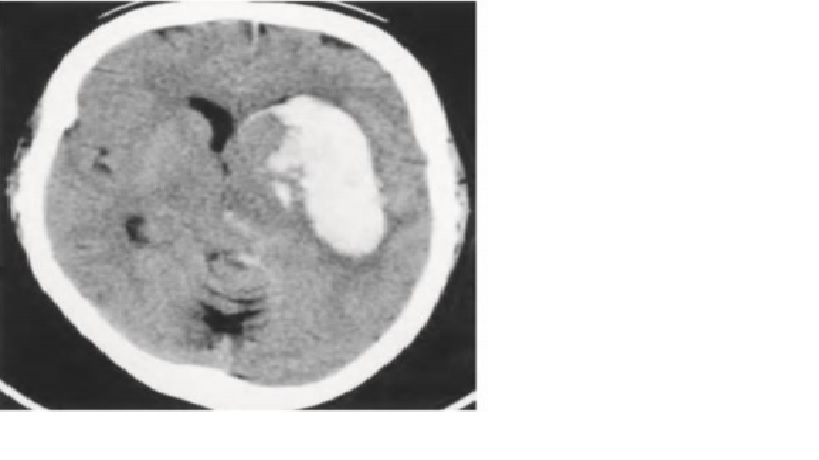

CT đầu không cản quang: xuất huyết putamen(T) lan vào não thất